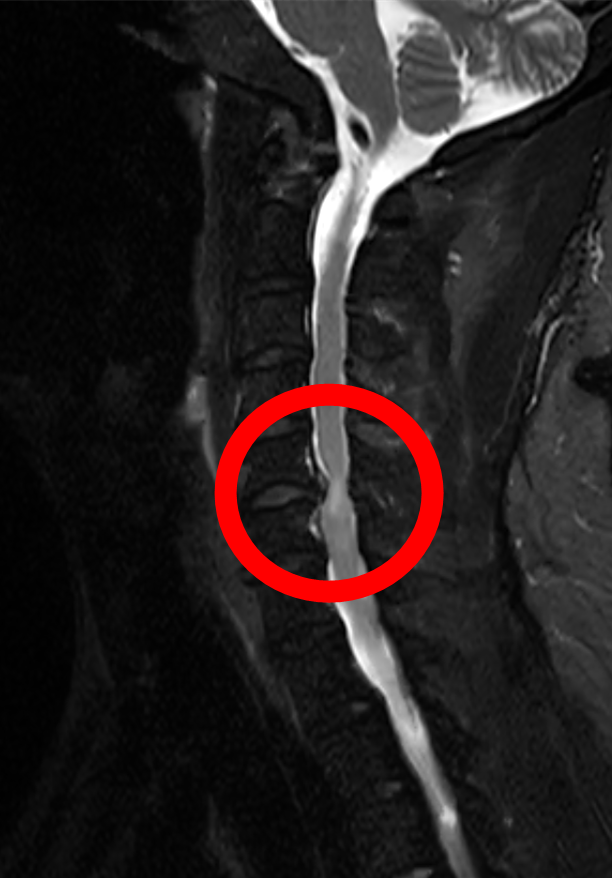

李先生谈及患病经历时满是感慨:“自从得了颈椎病,实在是太痛苦了,颈肩部疼痛,双上肢持续疼痛麻木,让人难以忍受,近期夜间更是因疼痛辗转难眠。”为缓解病痛,他尝试过口服中药、西药、理疗等多种保守治疗,但症状反复发作且逐渐加重,多次求医问诊效果均不理想。经我院脊柱外科团队详细检查,李先生被确诊为“颈椎间盘突出(C5-6 节段)伴脊髓压迫”。医生明确告知,若不及时手术,可能导致神经不可逆损伤,甚至出现瘫痪症状,需尽快干预治疗。

“传统颈椎融合术虽然能解除压迫,但失去一个椎间盘的活动单元后颈椎活动度会有减少,而李先生仅 45 岁,对颈椎活动需求比较高。” 经我院脊柱外科团队反复研讨,结合李先生的年龄和对颈部活动功能的需求,最终决定采用人工颈椎间盘置换术这一先进术式。该技术作为目前国际脊柱外科的主流前沿技术,打破了传统手术 “融合固定”的局限,具有技术更先进、创伤更微小、恢复更快捷三大核心优势。仿生假体模拟天然椎间盘功能,保留颈椎活动度,降低远期并发症风险;小切口、少出血,减少组织损伤和术后疼痛;术后无需长期制动,患者能快速回归正常工作生活。通过植入仿生人工椎间盘,既能彻底解除神经压迫,又能完整保留颈椎的屈伸、旋转功能,从根本上避免了传统手术带来的颈部僵硬问题。

手术当天,脊柱外科唐光副主任医师在高清显微镜的精准引导下,通过一个微创小切口,精准摘除病变椎间盘,植入适配的人工椎间盘假体,完美恢复颈椎正常生理曲度和椎间高度。整个手术出血量极少,神经保护精准到位,真正实现了 “微创、精准、安全” 的治疗目标。

术后恢复速度远超李先生预期:术后第 1天,颈肩疼痛和双上肢麻木症状就明显缓解,能够自主翻身、坐起;术后第2天,在医生指导下顺利下床行走,颈部活动灵活无受限,经影像学检查确认人工椎间盘位置精准、稳定性良好;术后第5天,李先生各项指标均达到出院标准,带着满意的笑容顺利出院。“原以为颈椎手术要躺很久,没想到这么快就能正常活动,医生技术太厉害了!”出院时,李先生带着家属,向脊柱外科团队表达了由衷的感谢。